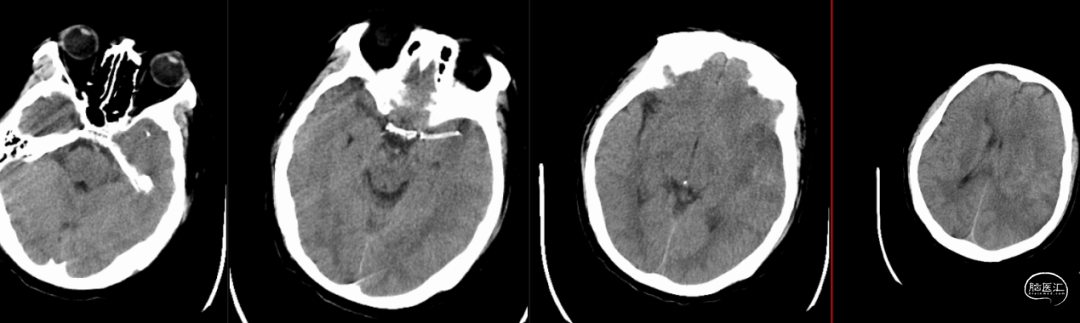

0.014" 微导丝引导下支架微导管进入M2下干,保留导丝退回微导管,造影提示M2未见显影,考虑“首过效应”阴性。此时考虑病变性质狭窄基础上并大负荷血栓可能,不排除栓塞性病变可能。

微导管到位左侧大脑中动脉下干,造影证实真腔。

沿微导管送入4.0*30mm Syphonet®取栓支架,造影显示:造影见左侧大脑中动脉M1段约1.8cm细长狭窄显影。大脑中动脉一干仍不显影,考虑狭窄明显并血栓形成。以静脉替罗非班推注12ml,同时静脉7ml/h维持。

沿4.0*30mm Syphonet®取栓支架输送导丝送入2.0*15mm SacSpeed®球囊扩张导管,于大脑中动脉狭窄段缓慢扩张成型后,保留Syphonet®取栓支架造影后提示远端血流改善。5分钟后支架锚定、负压下将6F Tethys®中间导引导管拟送至支架近端并接触血栓(中间导管无法到位),用50ml注射器保持抽吸管负压,回拉Syphonet®取栓支架,取出1枚2.0*2mm细小血栓。

取栓后复查造影见左侧大脑中动脉仍闭塞。

再次将4.0*30mm Syphonet®取栓支架释放到位并造影,见左侧大脑中动脉狭窄段仍明显,且靠近豆纹动脉处。

考虑狭窄明显并夹层形成,遂行4.5*22mm 自膨式闭环支架于左侧大脑中动脉水平段并造影。

最后路径手推造影,造影确认脑血流完全恢复,mTICI 3级。